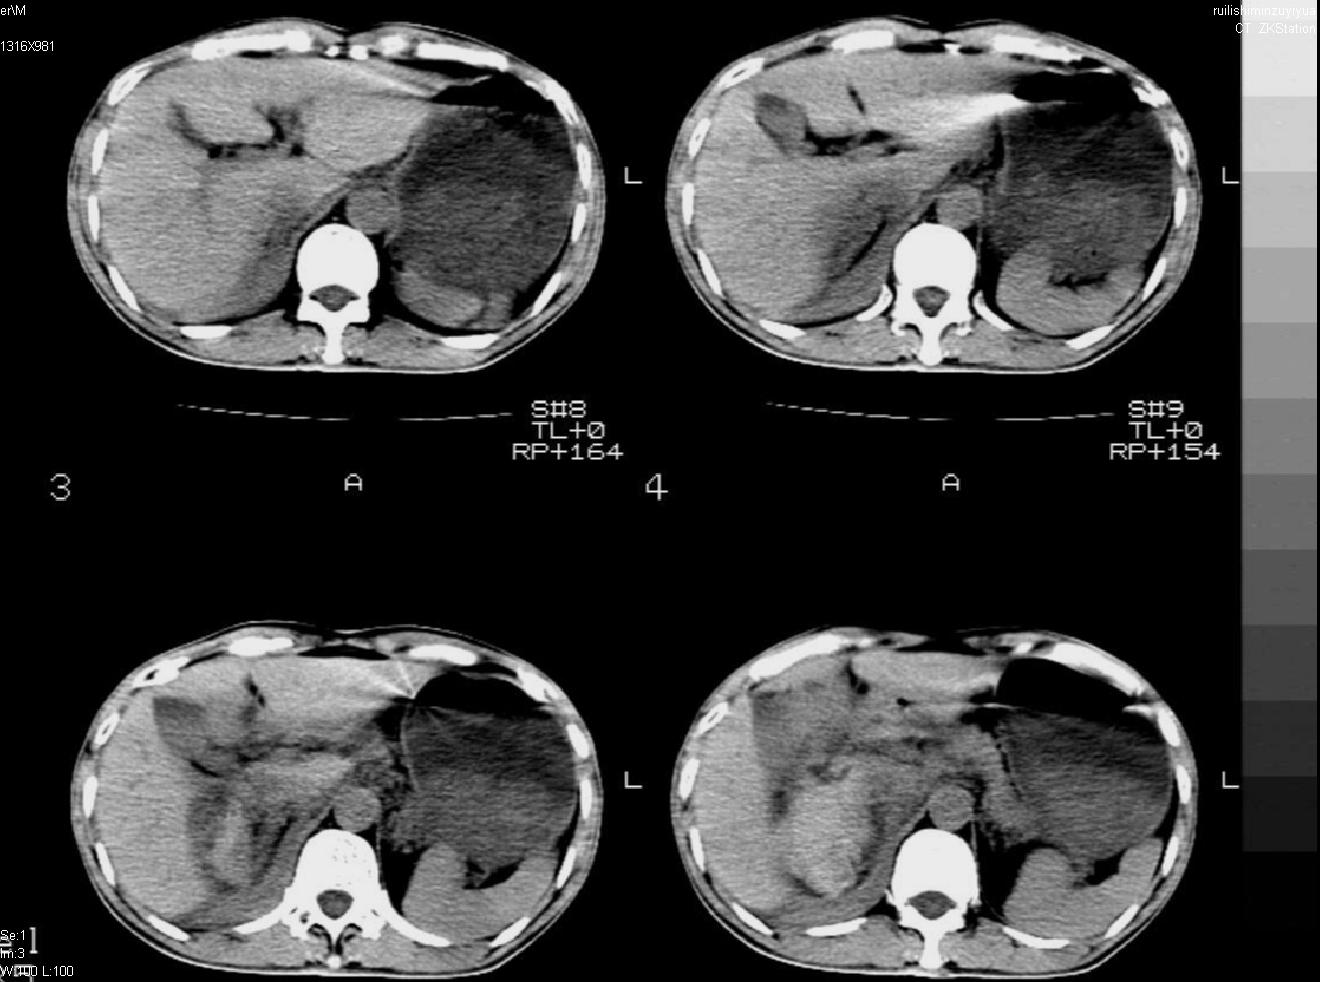

以下是引用liuyue在2007-12-3 6:27:00的发言:[br]右肾区可见密度不均匀、边缘欠清之肿块影,肾脏筋膜增厚,周围脂肪密度增高。右侧胸膜腔内可见少量液体密度影。考虑:1.右肾错构瘤(肾血管平滑肌脂肪瘤)可能性大。2.右侧少量胸腔积液。[br] 鉴别:1.肾脂肪肉瘤。2.肾平滑肌肉瘤。3.肾错构瘤恶变。